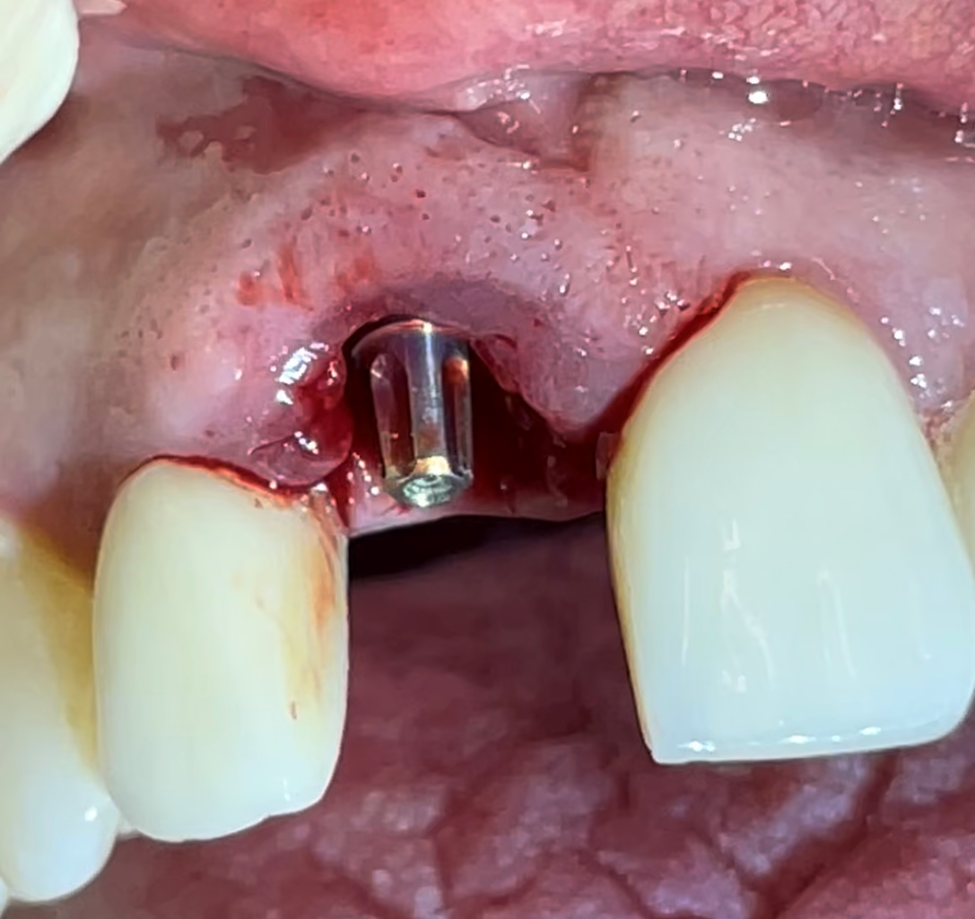

No presente caso, nossa paciente apresentou fratura (Figura 1) da raiz do elemento 11 (incisivo central superior direito), que já era reabilitado com pino intrarradicular (fibra de vidro + núcleo em resina) e coroa protética em cerâmica (dissilicato de lítio). Foi realizada exodontia minimamente traumática (Figuras 2 e 3), com manutenção das paredes ósseas e sem descolamento do tecido gengival ou abertura de retalho. Um implante Maestro (3.5 X 13 mm) foi instalado em posição tridimensional adequada e guiada pelo planejamento protético, no qual optamos por uma coroa parafusada (Figura 4). A profundidade de instalação foi conforme preconizada para um implante CM, e em seguida, um medidor de profundidade foi utilizado para selecionar o transmucoso do componente protético. Foi selecionado um pilar Ideale (3.3 X 4 mm) com transmucoso de 2.5 mm, favorecendo a adaptação dos tecidos moles e estabelecimento das distâncias biológicas peri-implantares (Figura 5).

O GAP foi preenchido com biomaterial Extra Graft, que foi facilmente condensado para dentro do alvéolo, no espaço entre o implante e a parede vestibular (Figura 6). Uma membrana de colágeno foi posicionada sobre o biomaterial, para protegê-lo na execução dos procedimentos protéticos (Figura 7).